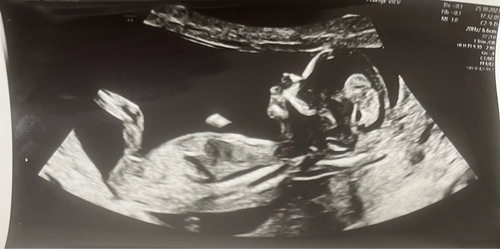

Ik deel hem nog eens, de meningen zijn verdeeld… 💙🩷?

12+6! 🥰 wat denken jullie?